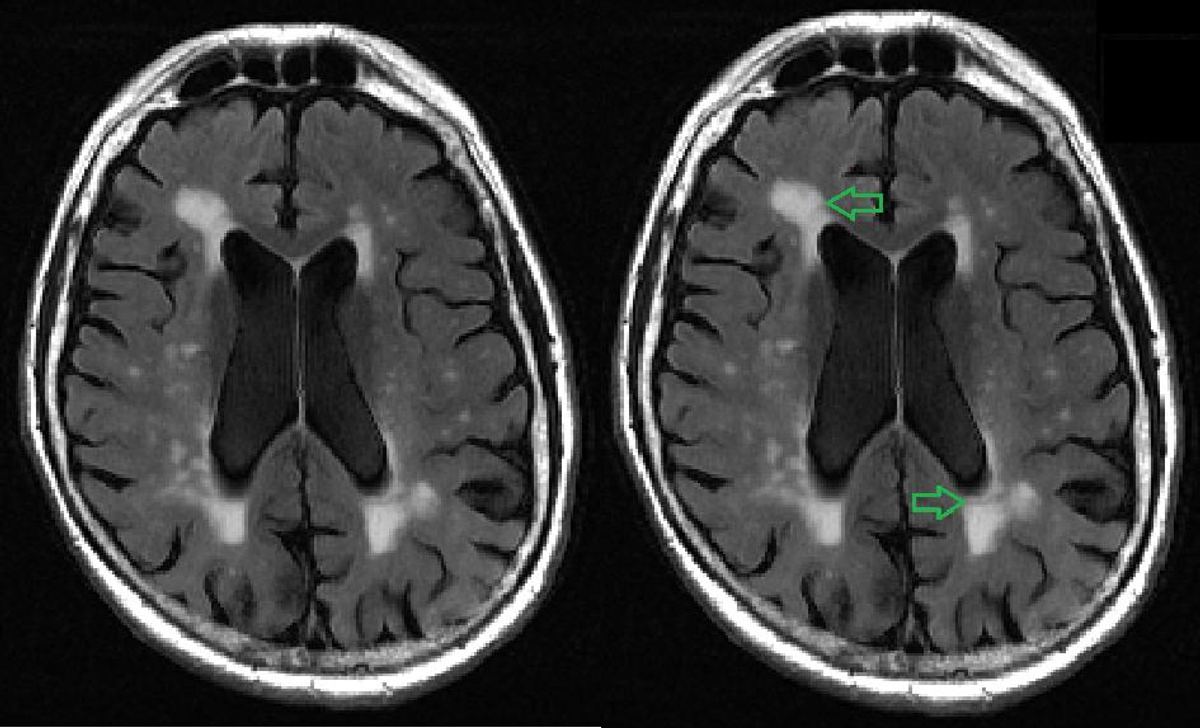

Cendre Mart lement Balcon White Spots On Mri Humain Manteau Ciel